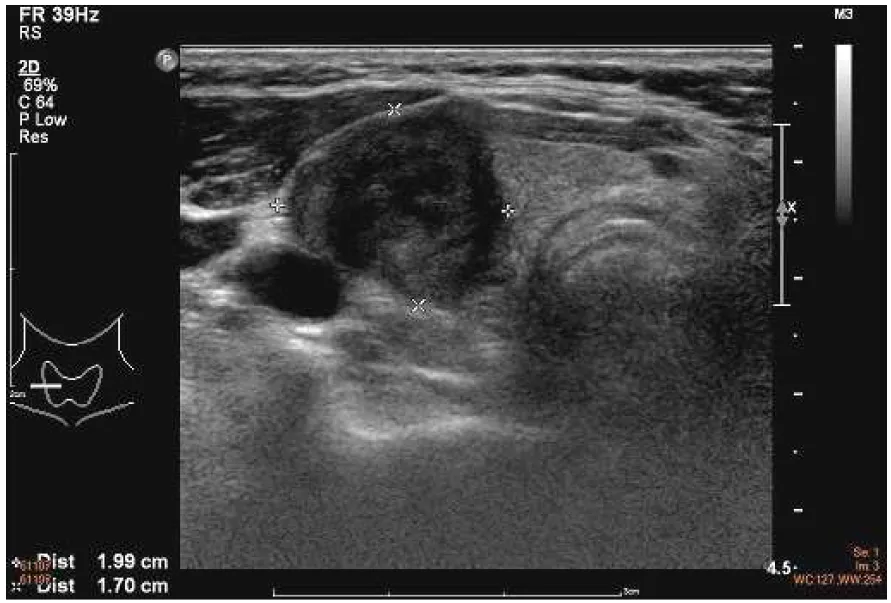

【111-2 醫學(五) 第41題】一位 65 歲男性發現右頸部有一硬塊,頸部超音波檢查如附圖,細針穿刺細胞學檢查顯示為甲狀腺乳突癌 (papillary thyroid cancer),根據超音波圖像,此甲狀腺癌可能合併下列何者特性?

這題的解題核心在於辨識甲狀腺結節的邊緣是否清晰完整,圖片中甲狀腺結節的邊緣模糊且不規則,顯示腫瘤已經突破甲狀腺包膜,侵犯到周圍組織。